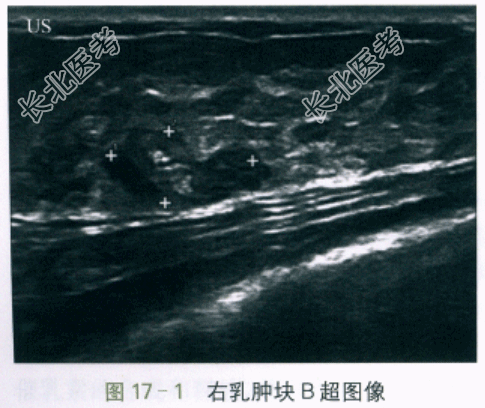

乳腺B超(见图17-1)提示:右侧乳腺可见一大小约22mm×18mm团块,位于约2点钟方向,水平位生长,呈不规则形,边界不清晰,边缘毛刺状,内部呈低回声,分布不均,可见散在细点状强回声,后方回声无明显改变。CDFI示内边缘见较丰富血流信号,血管较粗大,走行扭曲。三维超声显示团块边缘呈毛刺状,向周边不规则突起,未显示腺体和库氏韧带有异常聚集征象。双侧腋窝及锁骨上未见明显异常肿大淋巴结。诊断意见:右侧乳腺实质性团块,拟BI-RADS-US 4C类,请结合临床。钼靶检查(见图17-2)提示:右乳内上象限约2cm大小不规则占位伴不规则成簇细小钙化,拟BI-RADS 4C类。